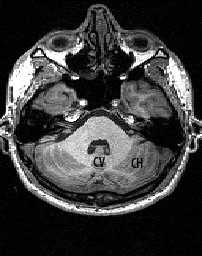

Кзади от моста и продолговатого мозга расположен мозжечок . Со стволом мозга он соединен верхней, средней и нижней ножками мозжечка. Состоит мозжечок из срединно расположенного червя и парных полушарий.

МРТ головного мозга. Аксиальный срез. Мозжечок (CV- червь мозжечка, CH - полушарие мозжечка).